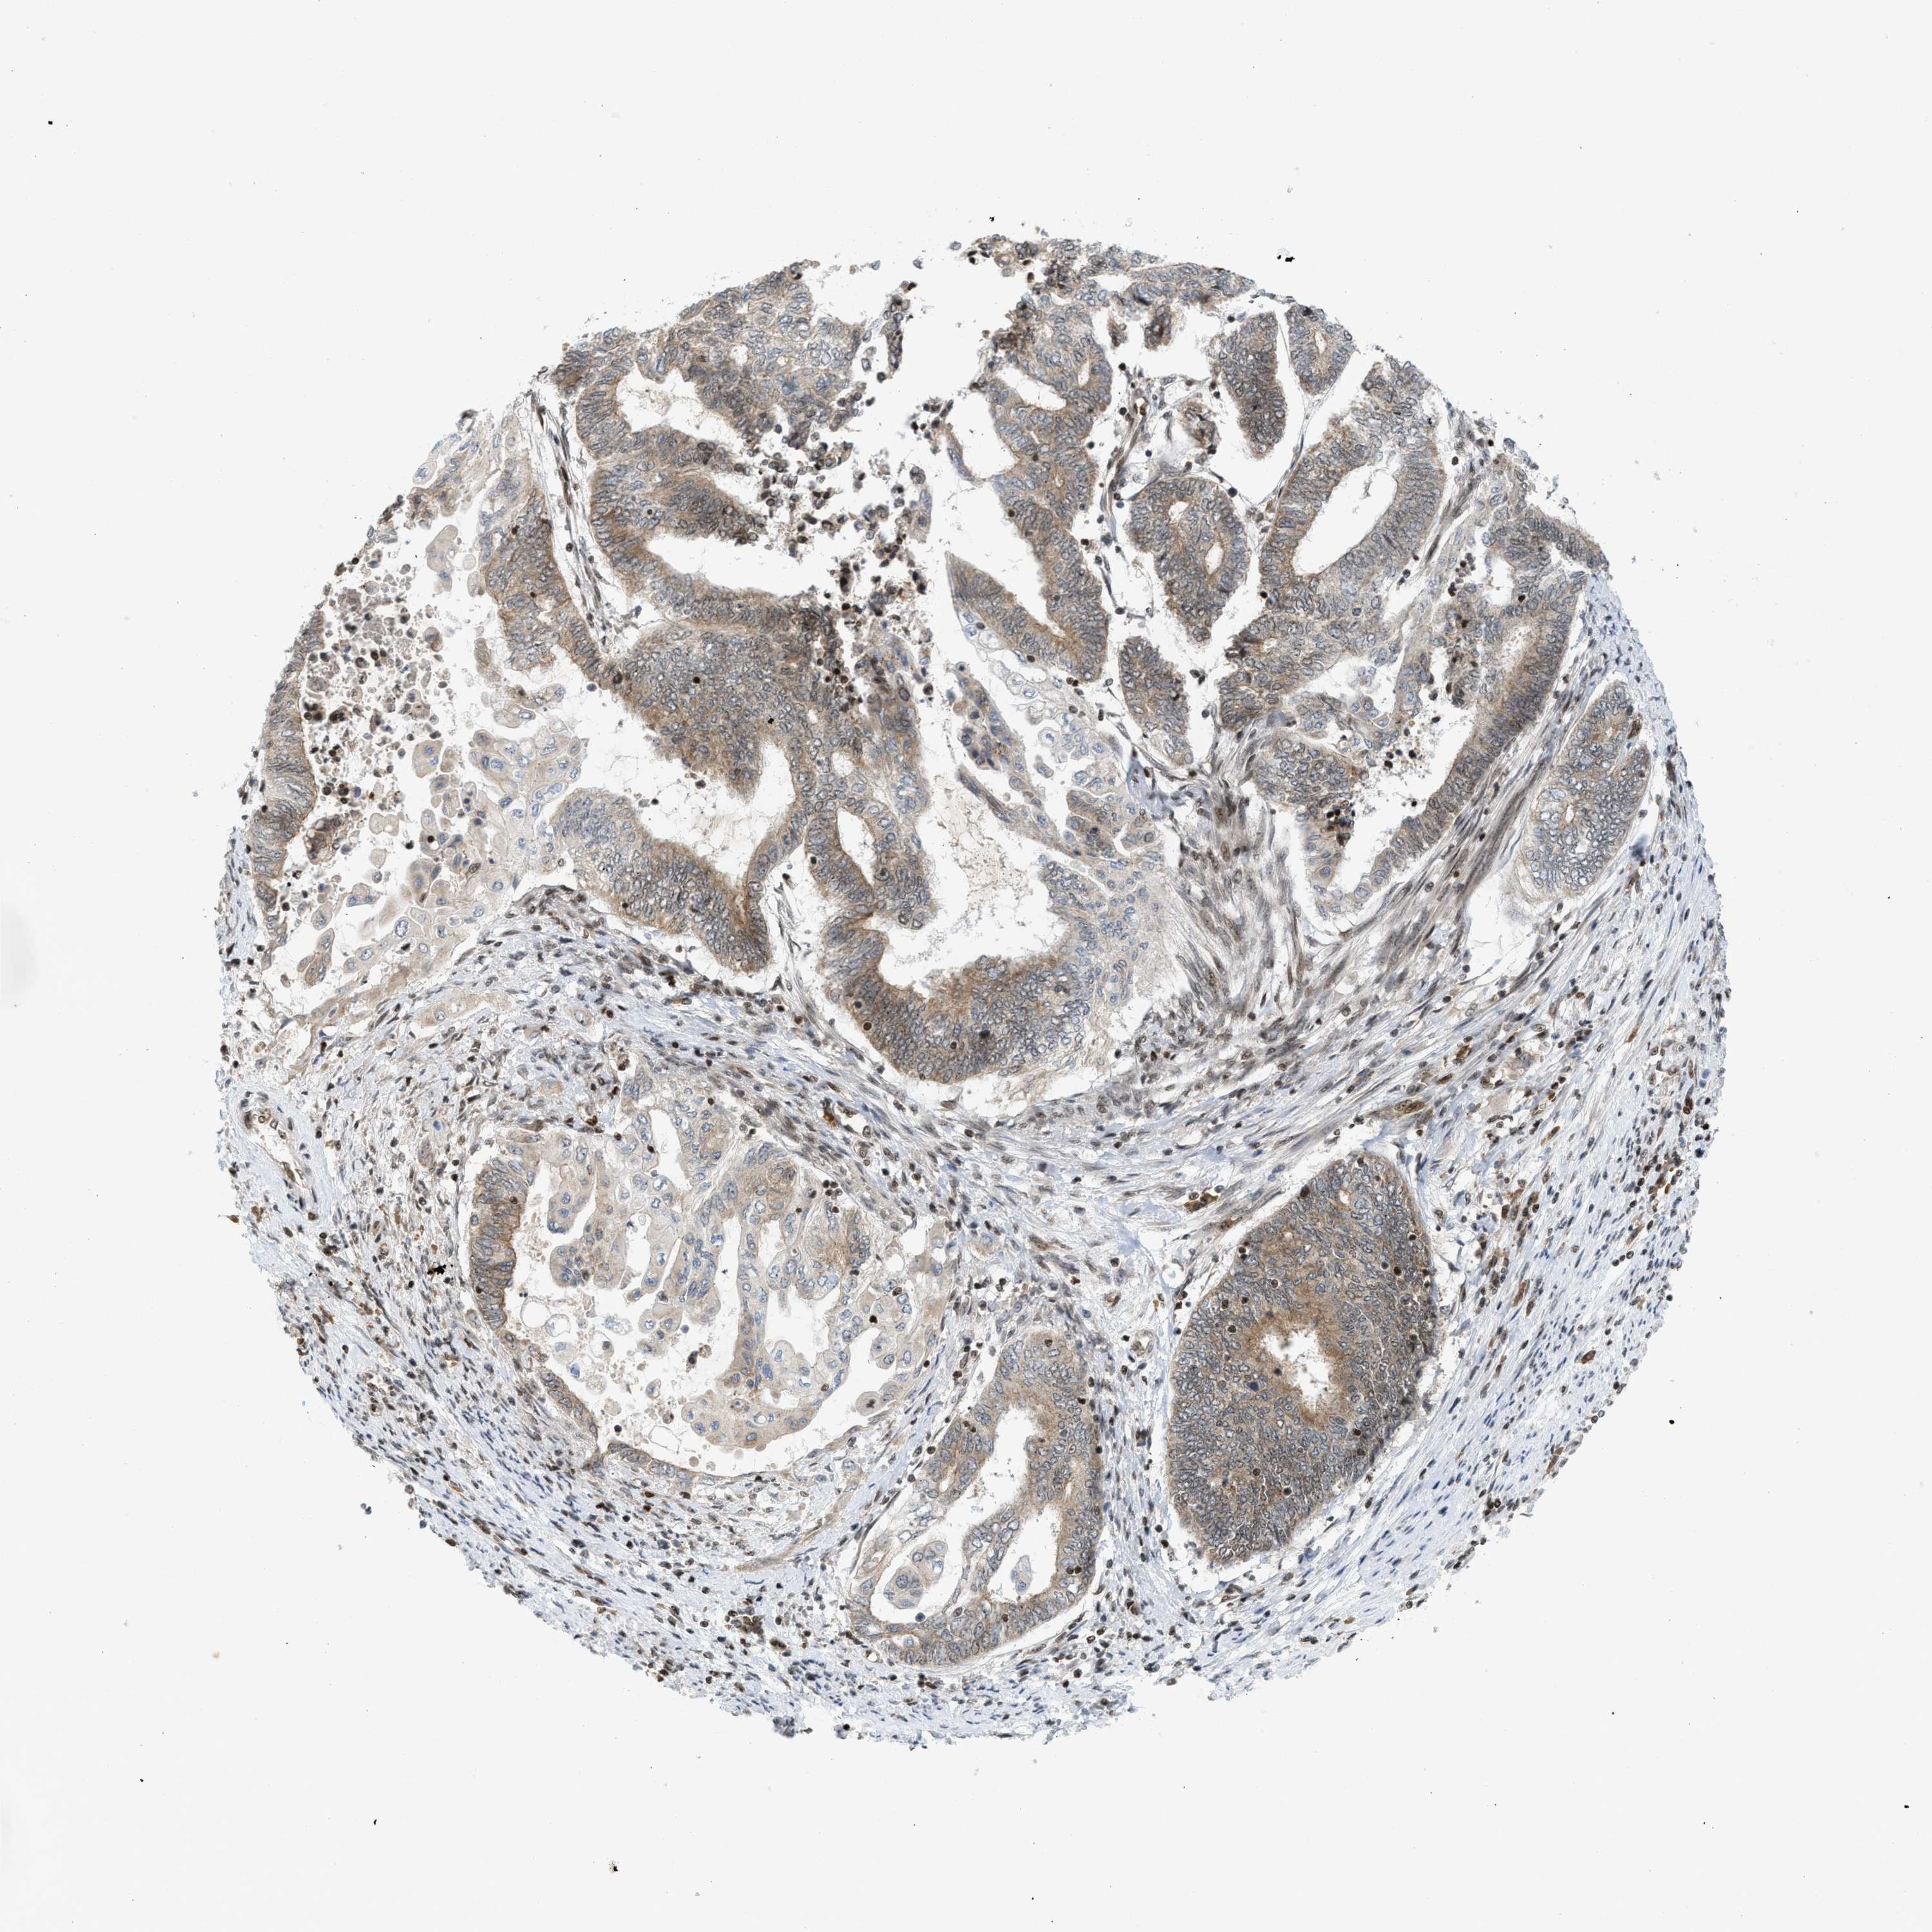

ENDOMETRIAL CANCER - Protein expressioni

A mouse-over function shows sample information and annotation data. Click on an image to view it in a full screen mode. Samples can be filtered based on level of antibody staining by selecting one or several of the following categories: high, medium, low and not detected. The assay and annotation is described here.

Note that samples used for immunohistochemistry by the Human Protein Atlas do not correspond to samples in the TCGA dataset.

Antibody stainingi

Antibody staining in the annotated cell types in the current human tissue is reported as not detected, low, medium, or high, based on conventional immunohistochemistry profiling in selected tissues. This score is based on the combination of the staining intensity and fraction of stained cells.

Each image is clickable and will lead to virtual microscopy that enables deeper exploration of all samples and also displays staining intensity scores, fraction scores and subcellular localization as well as patient and tissue information for each sample.

Antibody HPA016736

Staining

High

Medium

Low

Not detected

Intensity

Strong

Moderate

Weak

Negative

Quantity

>75%

75%-25%

<25%

None

Location

Nuclear

Cytoplasmic/membranous

Cytoplasmic/membranous,nuclear

Adenocarcinoma, NOS